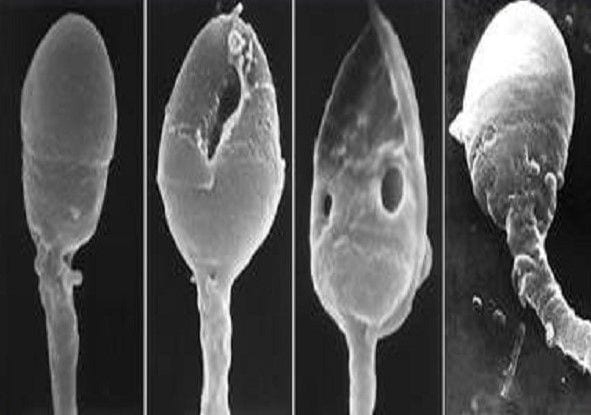

Jedoch haben neue wissenschaftliche Daten gezeigt, dass bestimmte Merkmale der Spermiummorphologie, wie zum Beispiel das Vorhandensein einiger „Blasen“ im Spermium darauf hinweist, dass die DNA des Spermiums pathologisch ist. Diese „Blasen“, auch Vakuolen genannt, waren aufgrund ihrer Größe mit den bisherigen Methoden nicht sichtbar, was zur Folge hatte, dass sich die IMSI-Technologie weiterentwickelt hat.

Die IMSI-Mikroskope ermöglichen durch spezielle Linsen die Vergrößerung der Spermien bis zu 10.000-mal. Somit haben wir die Möglichkeit, das Innere des Kopfes und mehrere Merkmale zu sehen, damit wir genau diejenigen Spermien auswählen können, die sich in ausgezeichnetem Zustand befinden.